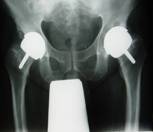

BHRX-ray BHRX-ray

In hip resurfacing, the hip joint is relined rather than replaced. The head and neck of the femur are preserved. The worn surfaces of the head and socket are carefully machined away with precision instruments. The joint is then lined with a metal covering for the head and socket.